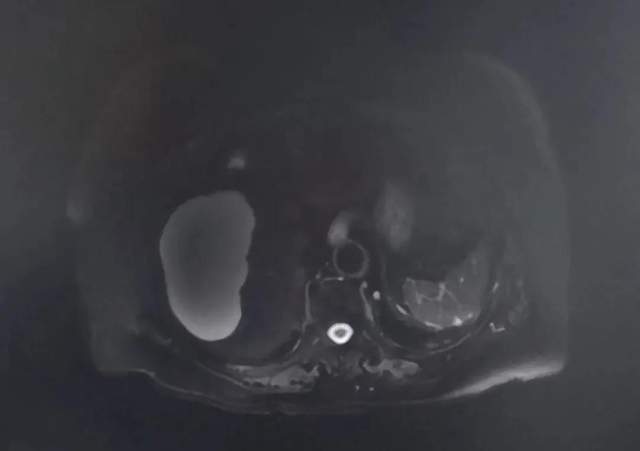

目前,第一次制定的治疗方案仍在继续当中,老人家肝脏病灶表现出持续缓解中,但乳房病灶稍有进展。由于,老人家存在一个互动配合困难的问题,局部治疗难以进行。

(第一次评估 肝脏病灶明显缩小)

(2020年11月25日)